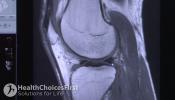

Registered massage therapists help with whiplash is an injury that you experience, that most people experience, from car accidents. You can also have it from a sports injury.The technical term for whiplash in the medical literature is whiplash associated disorders, or WAD, and that’s what we’re going to refer to it as today. WAD happens when your head is thrown about, usually forward and sometimes backwards and side to side and treatment from a local RMT Registered Massage Therapist .

It can be any other direction but that’s the general idea. And it’s an acceleration, deacceleration injury when the neck structures have to respond to that force that comes into you.The types of symptoms that you might expect after a car accident and a whiplash injury would be anywhere from moderate to no symptoms at all. And the moderate symptoms generally consist of stiffness in the neck, some mild achiness, maybe some mild headache, and you might feel that you’re more sensitive to cold than you normally are.

The more severe symptoms that people might feel are ringing in the ears, dizziness, loss of memory and pain coming down their arms. With whiplash injuries, there are many factors that go into deciding how much pain you’re going to be in.The force of the impact is one, and in some cases – not all cases – people have what they call low velocity injuries, where it’s a slow-moving, low-impact, but the patient experiences a lot of pain afterwards.